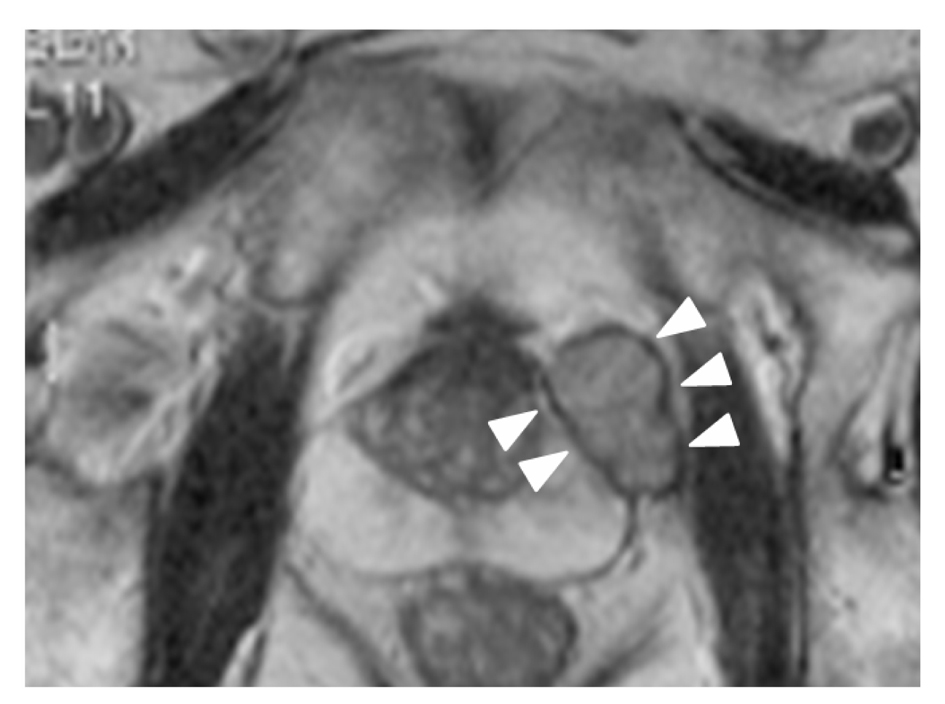

A 72-year-old man was referred to our hospital for treatment of prostatic cancer with atypical imaging findings. PSA level was elevated, at 11.3 ng/mL. Digital rectal examination revealed a non-movable nodule palpable at the left base of the prostate. Transrectal ultrasonography (TRUS) revealed an isoechoic mass above the prostate, and MRI showed a solitary mass with circumferential capsule above the prostate (Fig. 1). Although prostatic cancer had been diagnosed in the previous hospital based on needle biopsy, whether the prostatic cancer had developed in the mass or within the normal morphology of the prostate remained unclear. We recommended re-biopsy with the intent of confirming the site of prostatic cancer. TRUS-directed biopsy of the prostate and mass demonstrated adenocarcinoma only in the mass, and this adenocarcinoma showed positive results for PSA on immunohistochemical examination. No metastases were identified on CT or bone scintigraphy. Radical prostatectomy and pelvic lymphadenectomy were performed 2 months after diagnosis of prostatic carcinoma. The postoperative course has been uneventful and the patient is currently doing well, with no metastatic disease. As of 14 months postoperatively, PSA level has decreased below the level of detection (< 0.02 ng/mL).

![]() Click for large image | Figure 1. T2-weighted MRI, axial plane. A small, round encapsulated mass is apparent above the prostate. The mass is distinguishable from the prostate. |